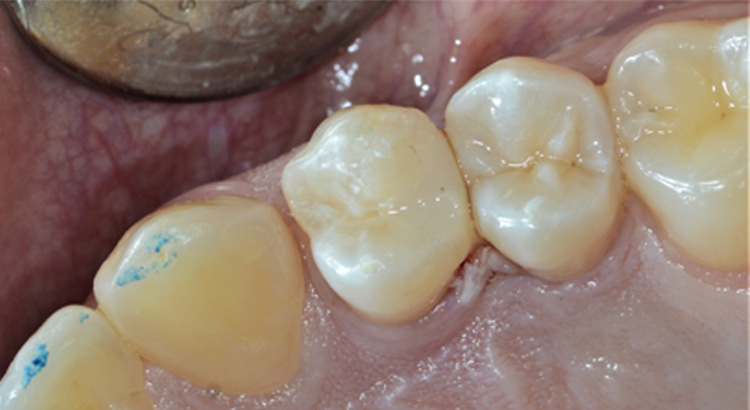

Conservativa

Il paziente non sapeva di avere una carie estesa tra i due premolari. Fortunatamente non procurava dolore e si è potuto salvare il dente con una ricostruzione in materiale composito e ristabilire il corretto rapporto tra i due denti.